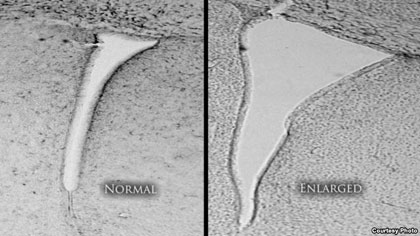

| Một bộ não chuột bị phơi nhiễm với không khí bị ô nhiễm cho thấy một não thất bên bị phình đại (bên phải) so với não bộ ở một con chuột với không khí sạch và được lọc. Não thất bên phình đại có liên quan ở người mắc bệnh tự kỷ và tâm thần phân liệt. |